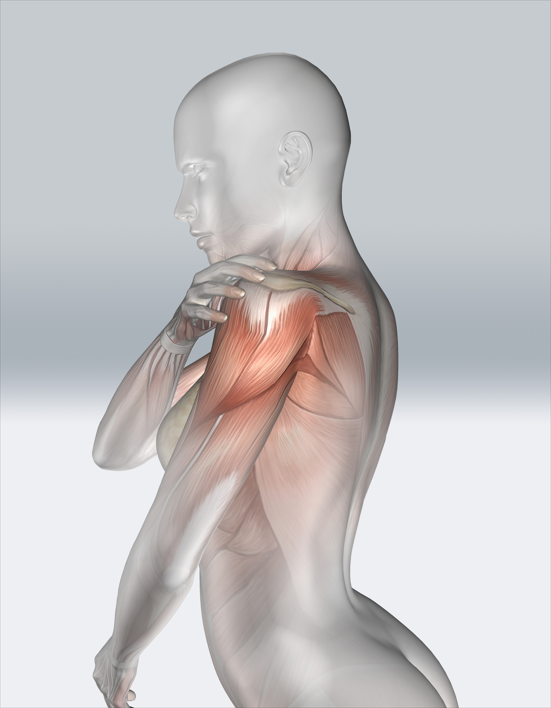

회전근개파열

회전근개파열은 어깨의 회전근개(어깨를 안정화하는 근육군)가 찢어져 어깨 통증과 기능 장애를 유발하는 상태입니다.

회전근개파열은 어깨의 회전근개를 구성하는 근육이나 힘줄이 부분적 또는 완전히 파열된 상태로, 보통 과도한 사용이나 외상으로 발생합니다. 이로 인해 어깨의 움직임과 기능에 심각한 제한이 생깁니다.